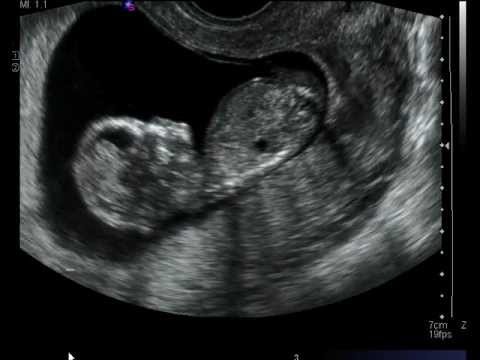

علامات الطفل المنغولي في السونار ، في بعض الاحيان حينما تجري الام بعض الفحوصات، يخبرها الاطباء باحتمالية أن طفلها سيكون منغوليًا أي مصابًا بمتلازمة داون، فهل تظهر بشكل اكيد علامات الطفل المنغولي في السونار ؟

يمكن معرفة علامات الطفل المنغولي في السونار عن طريق فحص الشفافية القفوية للجنين، ويتم ذلك من خلال فحص الفقرات العنقية الخاصة به خلال الفترة بين الأسبوع 11 إلى الأسبوع 13 من الحمل.

ويركز هذا الفحص على مساحة صغيرة توجد بالنسيج الموجود بمؤخرة عنق الجنين والذي يطلق عليها اسم الطية القفوية، وقد كشفت الدراسات أن تلك البقعة تقوم بجمع السائل القفوي، وفي حالة إذا أظهرت النتيجة وجود كمية أكبر من السائل القفوي، فإن احتمالية اصابة الجنين بأمراض اختلال الكروموسومات مثل متلازمة داون تصبح أكبر.

يمكن لهذا الفحص أن يكشف عن العيوب الخلقية التي تكون مصاحبة لمتلازمة داون مثل: وجود عيب بالجدار الاذيني البطيني للقلب، أو وجود عيوب بالأمعاء الدقيقة، أو عدم وجود عظام الأنف، أو وجود قصر بعظم الفخذ.

عيوب سونار الحمل للكشف عن الطفل المنغولي

لا تعد نتائج سونار الحمل دقيقة بالشكل الكافي، حيث إن قابليته في تحديد الاصابة بمتلازمة داون عن طريق فحص السائل القفوي تمثل 75% من الحالات، ويستطيع السونار أن يكشف حوالي 58% من حالات العيوب الخلقية المصاحبة لمتلازمة داون والتي من أبرزها غياب عظام الأنف.

واحيانا يمكن أن يقوم السونار بإعطاء نتيجة إيجابية خاطئة تشير لاصابة الطفل بمتلازمة داون، ولهذا لابد من التأكد من خلال اجراء كافة الفحوصات الاخرى للحصول على نتائج أكثر دقة.